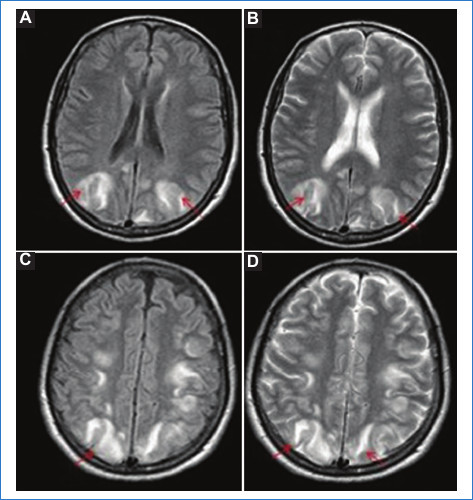

Hallazgos típicos: áreas con edema vasogénico caracterizadas por hiperintensidad en T2 y FLAIR e hipointensidad en T1 a nivel parieto-occipital bilateral. La difusión suele ser negativa, ya que se debe a edema vasogénico (Fig. 1). Sin embargo, cuando no se realiza un diagnóstico precoz puede evolucionar a edema citotóxico (irreversible), en cuyo caso dichas áreas presentan restricción en difusión con caída de señal en el mapa de ADC, o puede asociarse a la existencia de hemorragia subaracnoidea (HSA)1,4.

Hallazgos atípicos: es casi tan habitual como la clásica. Hay afectación de los lóbulos frontales, el tronco, el cerebelo y los ganglios basales. La mayoría de los casos remiten por completo. Las lesiones irreversibles (edema citotóxico) ocurren en el 15% de los casos y se caracterizan por restricción en difusión (Fig. 2)4.